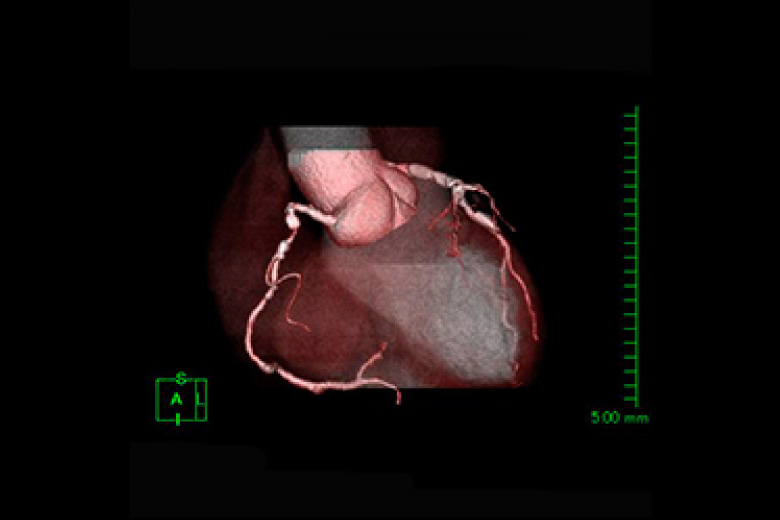

2台のマルチスライスCT(320列、64列)にて検査を行っております。

CTはX線管と検出器が体の周りを360°回転しコンピュータ処理により画像を作成します。

頭部・胸部・腹部・四肢など全身の撮影ができ、心臓(冠動脈)などの撮影も可能です。

320列CTにより全身をより短時間で撮影できるようになり、患者さんの負担が少なくなりました。また、320列CTでは16cmの範囲(頭部や心臓など)を1回転で撮影できます。

また逐次近似再構成により被ばくの少ない検査が受けられます。

冠動脈狭窄